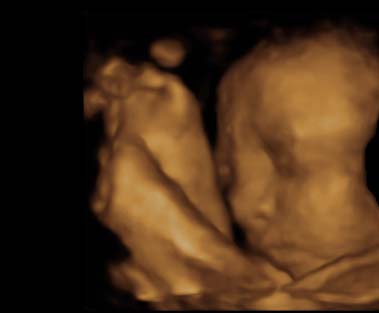

And although they couldn't find anything that would be causing the sharp pains, we were able to leave the office with this beauty...

Look at your little nose....You are so cute already, I can't wait to see you in person.